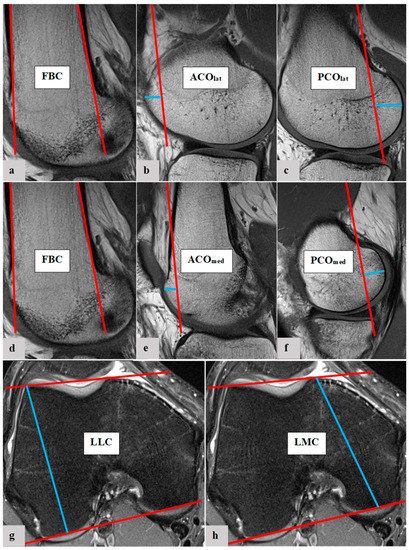

Figure 2.

Exemplary depiction of the determination of the femoral bone cortex (FBC, (a,d)) and the measurement of lateral anterior femoral condylar offset (ACOlat, (b)), lateral posterior femoral condylar offset (PCOlat, (c)), medial anterior femoral condylar offset (ACOmed, (e)), medial posterior femoral condylar offset (PCOmed, (f)), length of lateral femoral condyle (LLC, (g)) and length of medial femoral condyle (LMC, (h)): The determination of FBC as well as measurements of ACOlat, PCOlat, ACOmed and PCOmed were all performed in sagittal view of the knee joint in MRIs. To measure the femoral condylar offset parameters, the anterior and posterior femoral shaft bone cortex were determined in the sagittal view (a,d). Using CentricityTM Universal Viewer (RA1000, edition 2019, Buckinghamshire, Great Britain), the positions of the anterior and posterior femoral shaft axes were projected in the image, which best represented the anterior/posterior femoral condyle. The distance between the cortical bone of the anterior femoral condyle and the anterior cortex axis defines the ACO (b,e). According to the same principles, the PCO was defined in the posterior compartment. The distance between posterior cortex axis and posterior cortical condylar bone was measured (c,f). ACO and PCO were measured in the medial and lateral knee joint compartments. LLC and LMC were measured in the axial view. To define LLC and LMC, a tangent was applied to both the anterior and posterior cortical borders of the femoral condyles. The widest distance between these was measured for the lateral (g) and medial condyles (h).